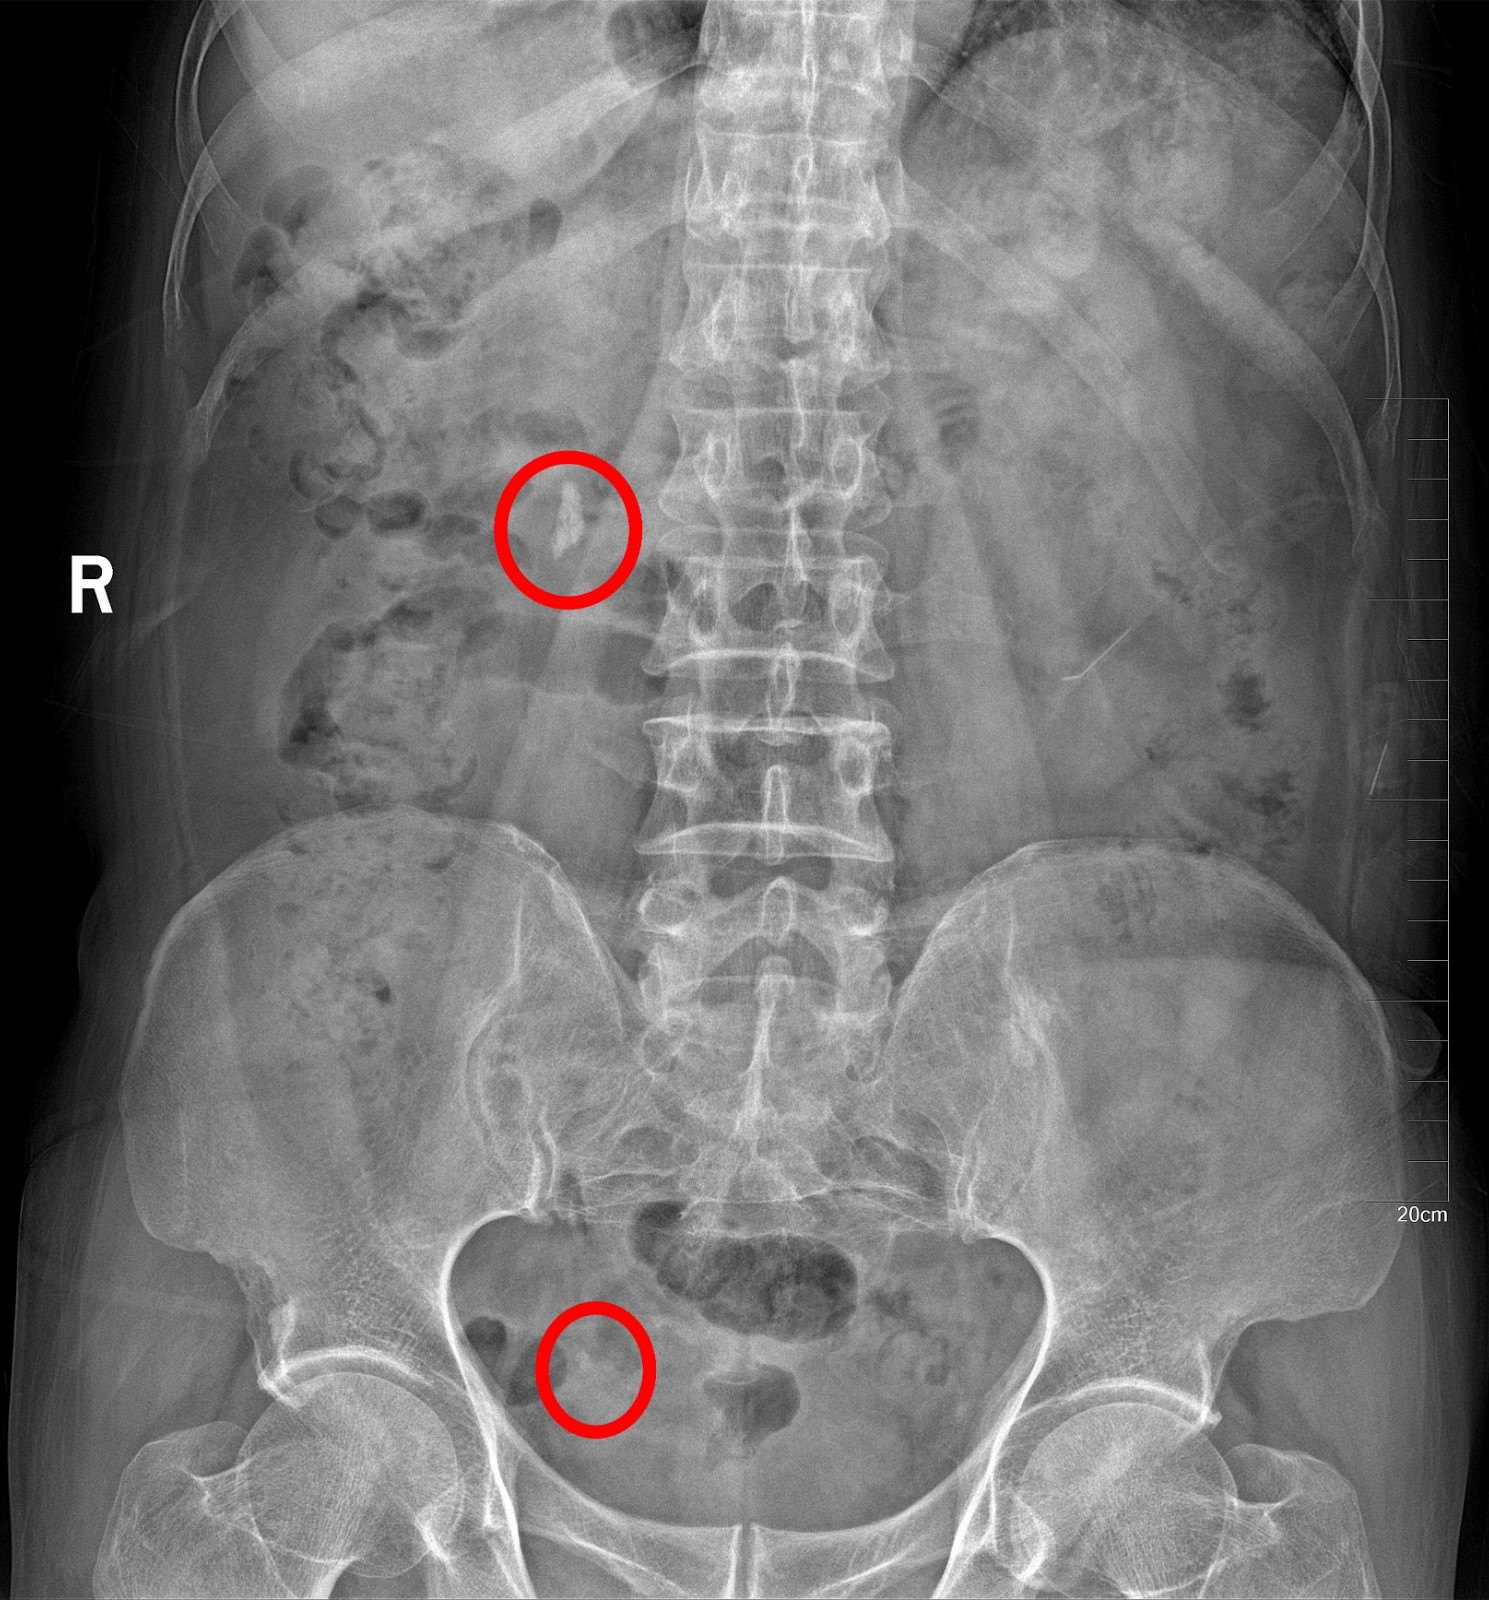

0.7厘米结石卡在输尿管下段

1、07cm的结石卡在输尿管下段可以考虑碎石,但具体方案需根据实际情况选择1 保守治疗 对于07cm的输尿管下段结石,首先可以考虑保守治疗 主要方法是增加饮水量至每日3000mL以上,并增加运动量,如跳绳跑步,以促进...